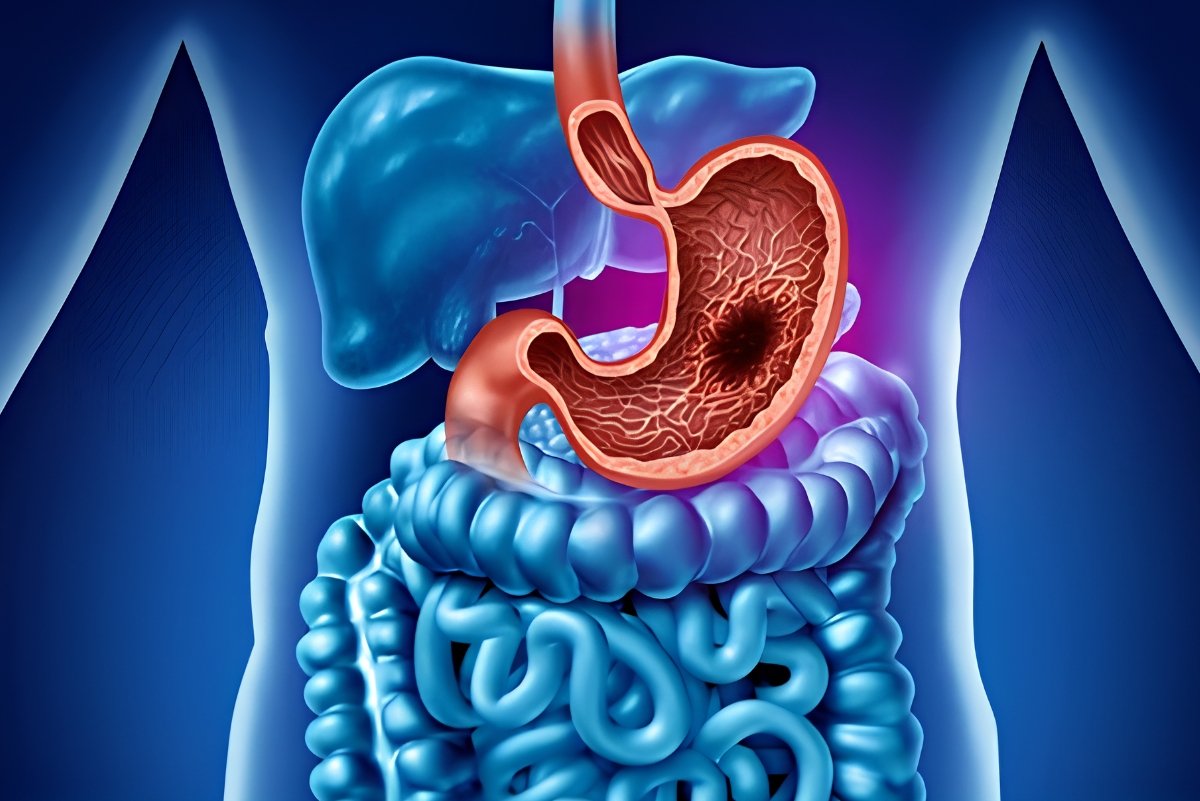

Could Constant Bloating Be a Sign of Stomach Cancer?